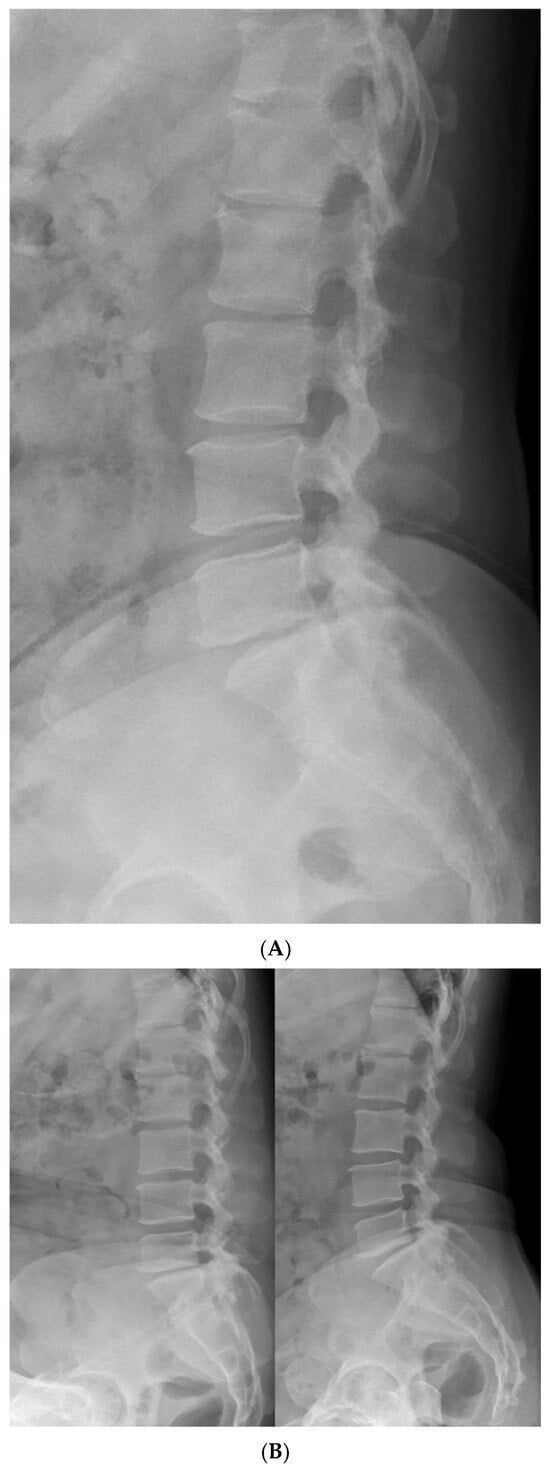

Further imaging evaluation was performed to confirm the previously diagnosed L5 bilateral pedicle fracture and to assess the involvement of surrounding structures. Figure 1A shows a plain radiograph taken during the initial examination in our hospital, revealing a subtly visible fracture at the pedicle of L5 and suspicious Meyerding grade 1 spondylolisthesis at the L5-S1 vertebrae. As shown in Figure 1B, dynamic flexion-extension lateral radiographs were performed to assess instability that could affect the treatment approach, and no abnormal findings were observed. Figure 1C shows a CT scan confirming isolated bilateral pedicle fractures at L5, consistent with the findings from the previous examination at the local clinic, and no additional fractures were identified. There were no sclerotic changes surrounding the fracture lines or pseudoarthrosis, suggesting an acute fracture despite the absence of recent trauma history. Pars defects or hypoplastic neural arch were not observed. Figure 2 shows MRI findings demonstrating low signal intensity on T1 and T2 weighted images in the bilateral pedicle lesions, consistent with acute lesions, and minimal hyperintense marrow edema surrounding the fracture lines on T2. Additionally, imaging revealed mild degenerative changes, including disc bulging at L3–4, L4–5, and L5–S1, and Modic type 2 at L5–S1. These disc lesions showed no features suggestive of an acute rupture and were more compatible with chronic degenerative changes rather than acute pathology. Given the absence of pre-existing LBP or neurologic symptoms, these degenerative findings were regarded as incidental and unrelated to the patient’s current presentation.

Figure 1. Initial radiologic evaluation at the first visit to our hospital. (A) The image shows a subtly visible fracture at the pedicle of L5 and Meyerding grade 1 spondylolisthesis at the L5–S1 level. (B) Flexion–extension lateral radiographs showing no relative sagittal plane translation between L5 and S1. (C) CT images confirming isolated bilateral pedicle fractures at L5 without additional fractures. No sclerotic change, pseudoarthrosis, or pars defect was observed, consistent with an acute fracture.